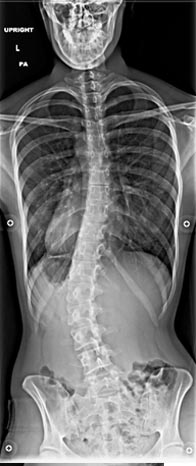

20 year old with severe low back pain from untreated idiopathic adolescent scholiosis who failed all conservative treatment with documented progression of scoliosis despite being done growing.